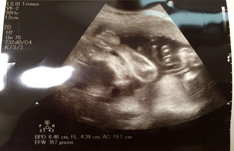

妊婦健診でした。 妊娠5ヶ月目から、先生と助産師さん交代で検診してもらっていまして、 今回は助産師さんによる検診でした。 といっても、特に特別な内容はなく、普通通りです。 色々測ってもらい、別に異常はないですねーということで、エコー。 今回のエコーでは、赤ちゃんの大きさなど色々と測ってもらえました。 里帰り先の病院では、1週間プラスくらいの大きさでしたが、 今回測ってもらったサイズだと、週数通りもしくは小さめな大きさでした。 ま、多少の誤差はでるだろう。。ということで、あまり気にしないことに...

妊娠8ヵ月:28-31週(2013/12/21-2014/1/17)。 8ヵ月目はいよいよ真面目に出産準備に取りかかり始めた感じです。 年末年始を挟んでいたため、気分的にも余裕ができて助かりました[:ぴかぴか:] たまごちゃんの様子 いつも通り2~3週間大き目のまま育ってくれています。 計画出産になったため、予定日が2週間短縮されましたがちょうどいいかも。 1/17(31週6日) BPD(児頭大横径) 84.8mm 34週5日相当 AC(腹部周囲長) 270.9mm 33週2日相当 FL(大腿骨...

8ヵ月−31週6日。 今日はいつものクリニックで検診。 次回からは里帰り先の病院で受診するため、こちらは今日が最終日。 今まで散々脅されてきたけれど、今日でやっと解放される〜[:植物:] さて、今日の測定内容はこんな感じ。 BPD(児頭大横径) 84.8mm 34週5日相当 AC(腹部周囲長) 270.9mm 33週2日相当 FL(大腿骨長)※太ももの長さ 62.5mm 34週6日相当 EFW(超音波胎児推定体重) 2028g 33週2日相当 逆子もち...